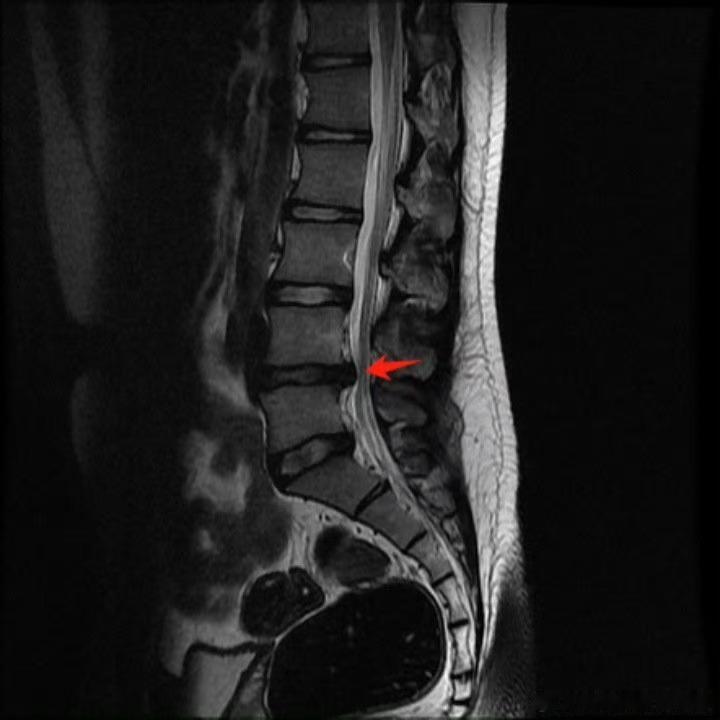

腰椎间盘突出 【腰突总担心要手术?】这个话题,我在线下初诊或答疑中常常遇到,今天